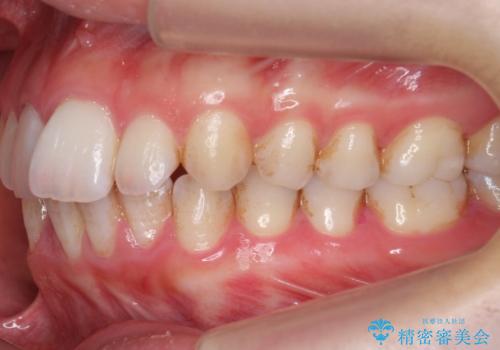

- 表面の着色を気にされて、ご来院されました。

お話しをしたところ、リーズナブルに短時間で綺麗にしたいとの事でした。

そこでPMTCの30分コースで、目立つ部分を中心に落としていきました。

タバコのヤニ・茶渋などの歯の着色除去は、保険適用外になります。

当院ではブラシ・クリームで研磨するPMTCに加え、

細かい所まで着色除去できるエアフローも取り揃えておりますので、